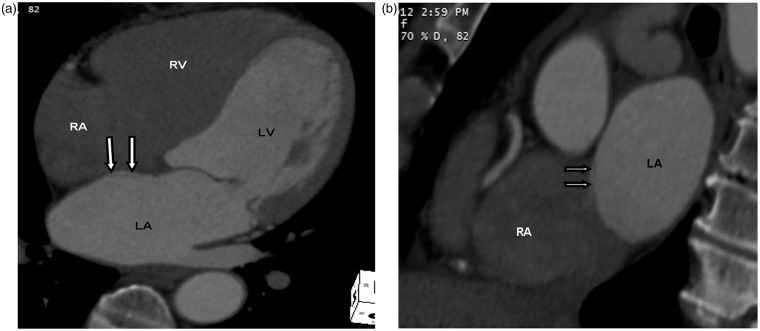

Advances in computed tomography have led to continuous improvement in cardiac imaging. Dedicated postprocessing capabilities, faster scan times, and cardiac gating methods reveal details of normal cardiac anatomy and anatomic variants that can mimic pathologic conditions. This article will review normal cardiac anatomy and variants that can mimic disease. Radiologists should be familiar with normal cardiac anatomy and anatomic variants to avoid misinterpretation of normal findings for pathologic processes.